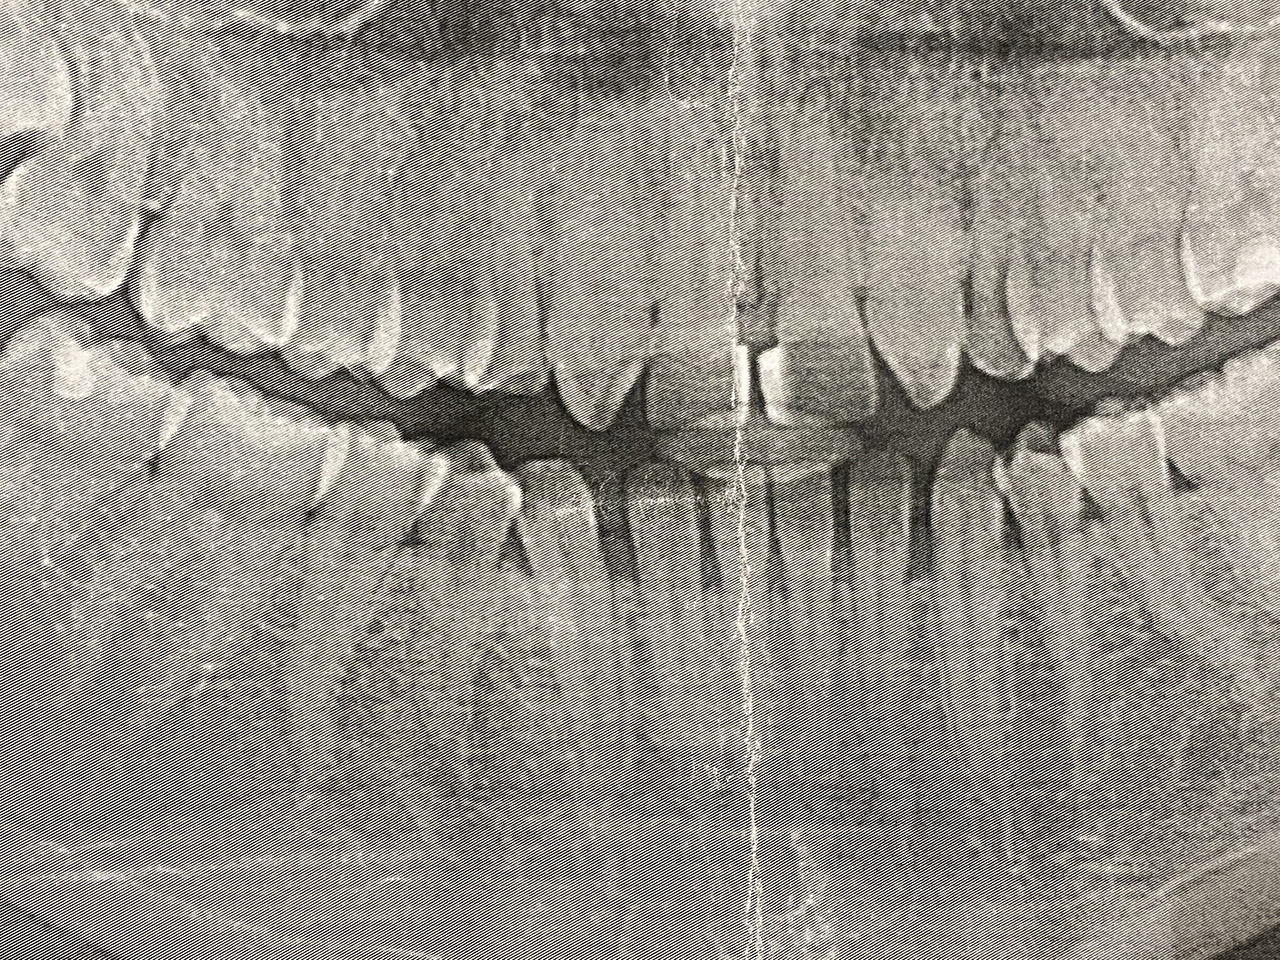

Ästhetische Zahnheilkunde / der komplexe Fall

Aplasien/Nichtanlagen, dadurch bleibende Milchzähne, Diasteme/Zahnlücken,

Bleaching/Bleichen, Positionierung der Zähne/Kieferorthopädie (Dr. Maija Eltz), Verblendung mit Veneers/Keramikschalen.